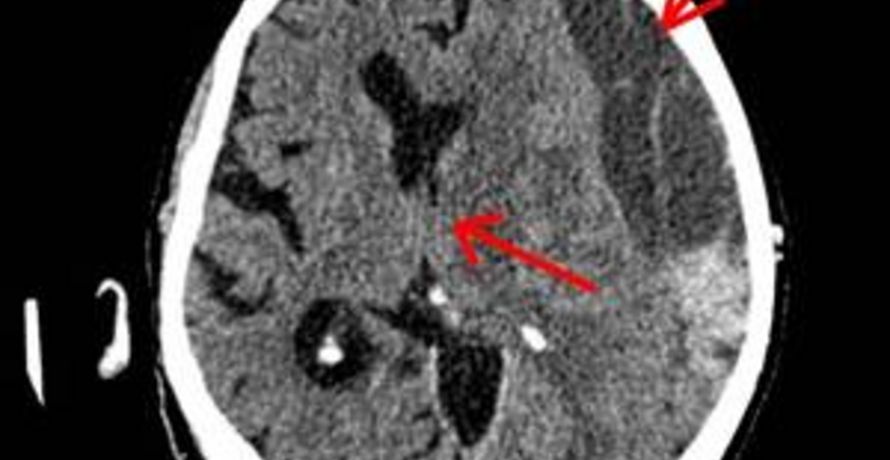

A traumatic brain injury is the result of external violence to the head. This results in a functional disorder or injury to the brain and/or its membranes such as the meninges, bony skull, skin or the vessels supplying the brain. It is common to categorise the severity of a traumatic brain injury based on the brain functions: best eye opening, best motor response and best verbal response (Glasgow Coma Score) into mild, moderate and severe traumatic brain injury. Head injuries without functional disorders of the brain or injuries to the brain are called cranial contusions.

Traumatic brain injury represents a significant medical, psychological, economic and financial problem in our society. Prevention and advances in pre-hospital care, the rapid diagnostic capabilities of computed tomography and the understanding of the pathophysiology of traumatic brain injury have led to a reduction in severe traumatic brain injury and more frequent survival. Nevertheless, brain injury is one of the most common causes of mortality in humans under the age of 45 and often results in physical and/or neuro-psychological disability.